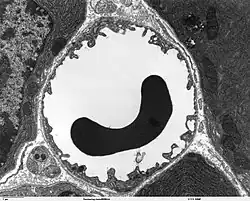

A capillary is a small blood vessel, from 5 to 10 micrometres in diameter, and is part of the microcirculation system. Capillaries are microvessels and the smallest blood vessels in the body. They are composed of only the tunica intima (the innermost layer of an artery or vein), consisting of a thin wall of simple squamous endothelial cells.[2] They are the site of the exchange of many substances from the surrounding interstitial fluid, and they convey blood from the smallest branches of the arteries (arterioles) to those of the veins (venules). Other substances which cross capillaries include water, oxygen, carbon dioxide, urea,[3] glucose, uric acid, lactic acid and creatinine. Lymph capillaries connect with larger lymph vessels to drain lymphatic fluid collected in microcirculation.

Blood capillaries are categorized into three types: continuous, fenestrated, and sinusoidal (also known as discontinuous).

Sinusoidal capillaries or discontinuous capillaries are a special type of open-pore capillary, also known as a sinusoid,[13] that have wider fenestrations that are 30–40 micrometres (μm) in diameter, with wider openings in the endothelium.[14] Fenestrated capillaries have diaphragms that cover the pores whereas sinusoids lack a diaphragm and just have an open pore. These types of blood vessels allow red and white blood cells (7.5 μm – 25 μm diameter) and various serum proteins to pass, aided by a discontinuous basal lamina. These capillaries lack pinocytotic vesicles, and therefore use gaps present in cell junctions to permit transfer between endothelial cells, and hence across the membrane. Sinusoids are irregular spaces filled with blood and are mainly found in the liver, bone marrow, spleen, and brain circumventricular organs.[14][15]